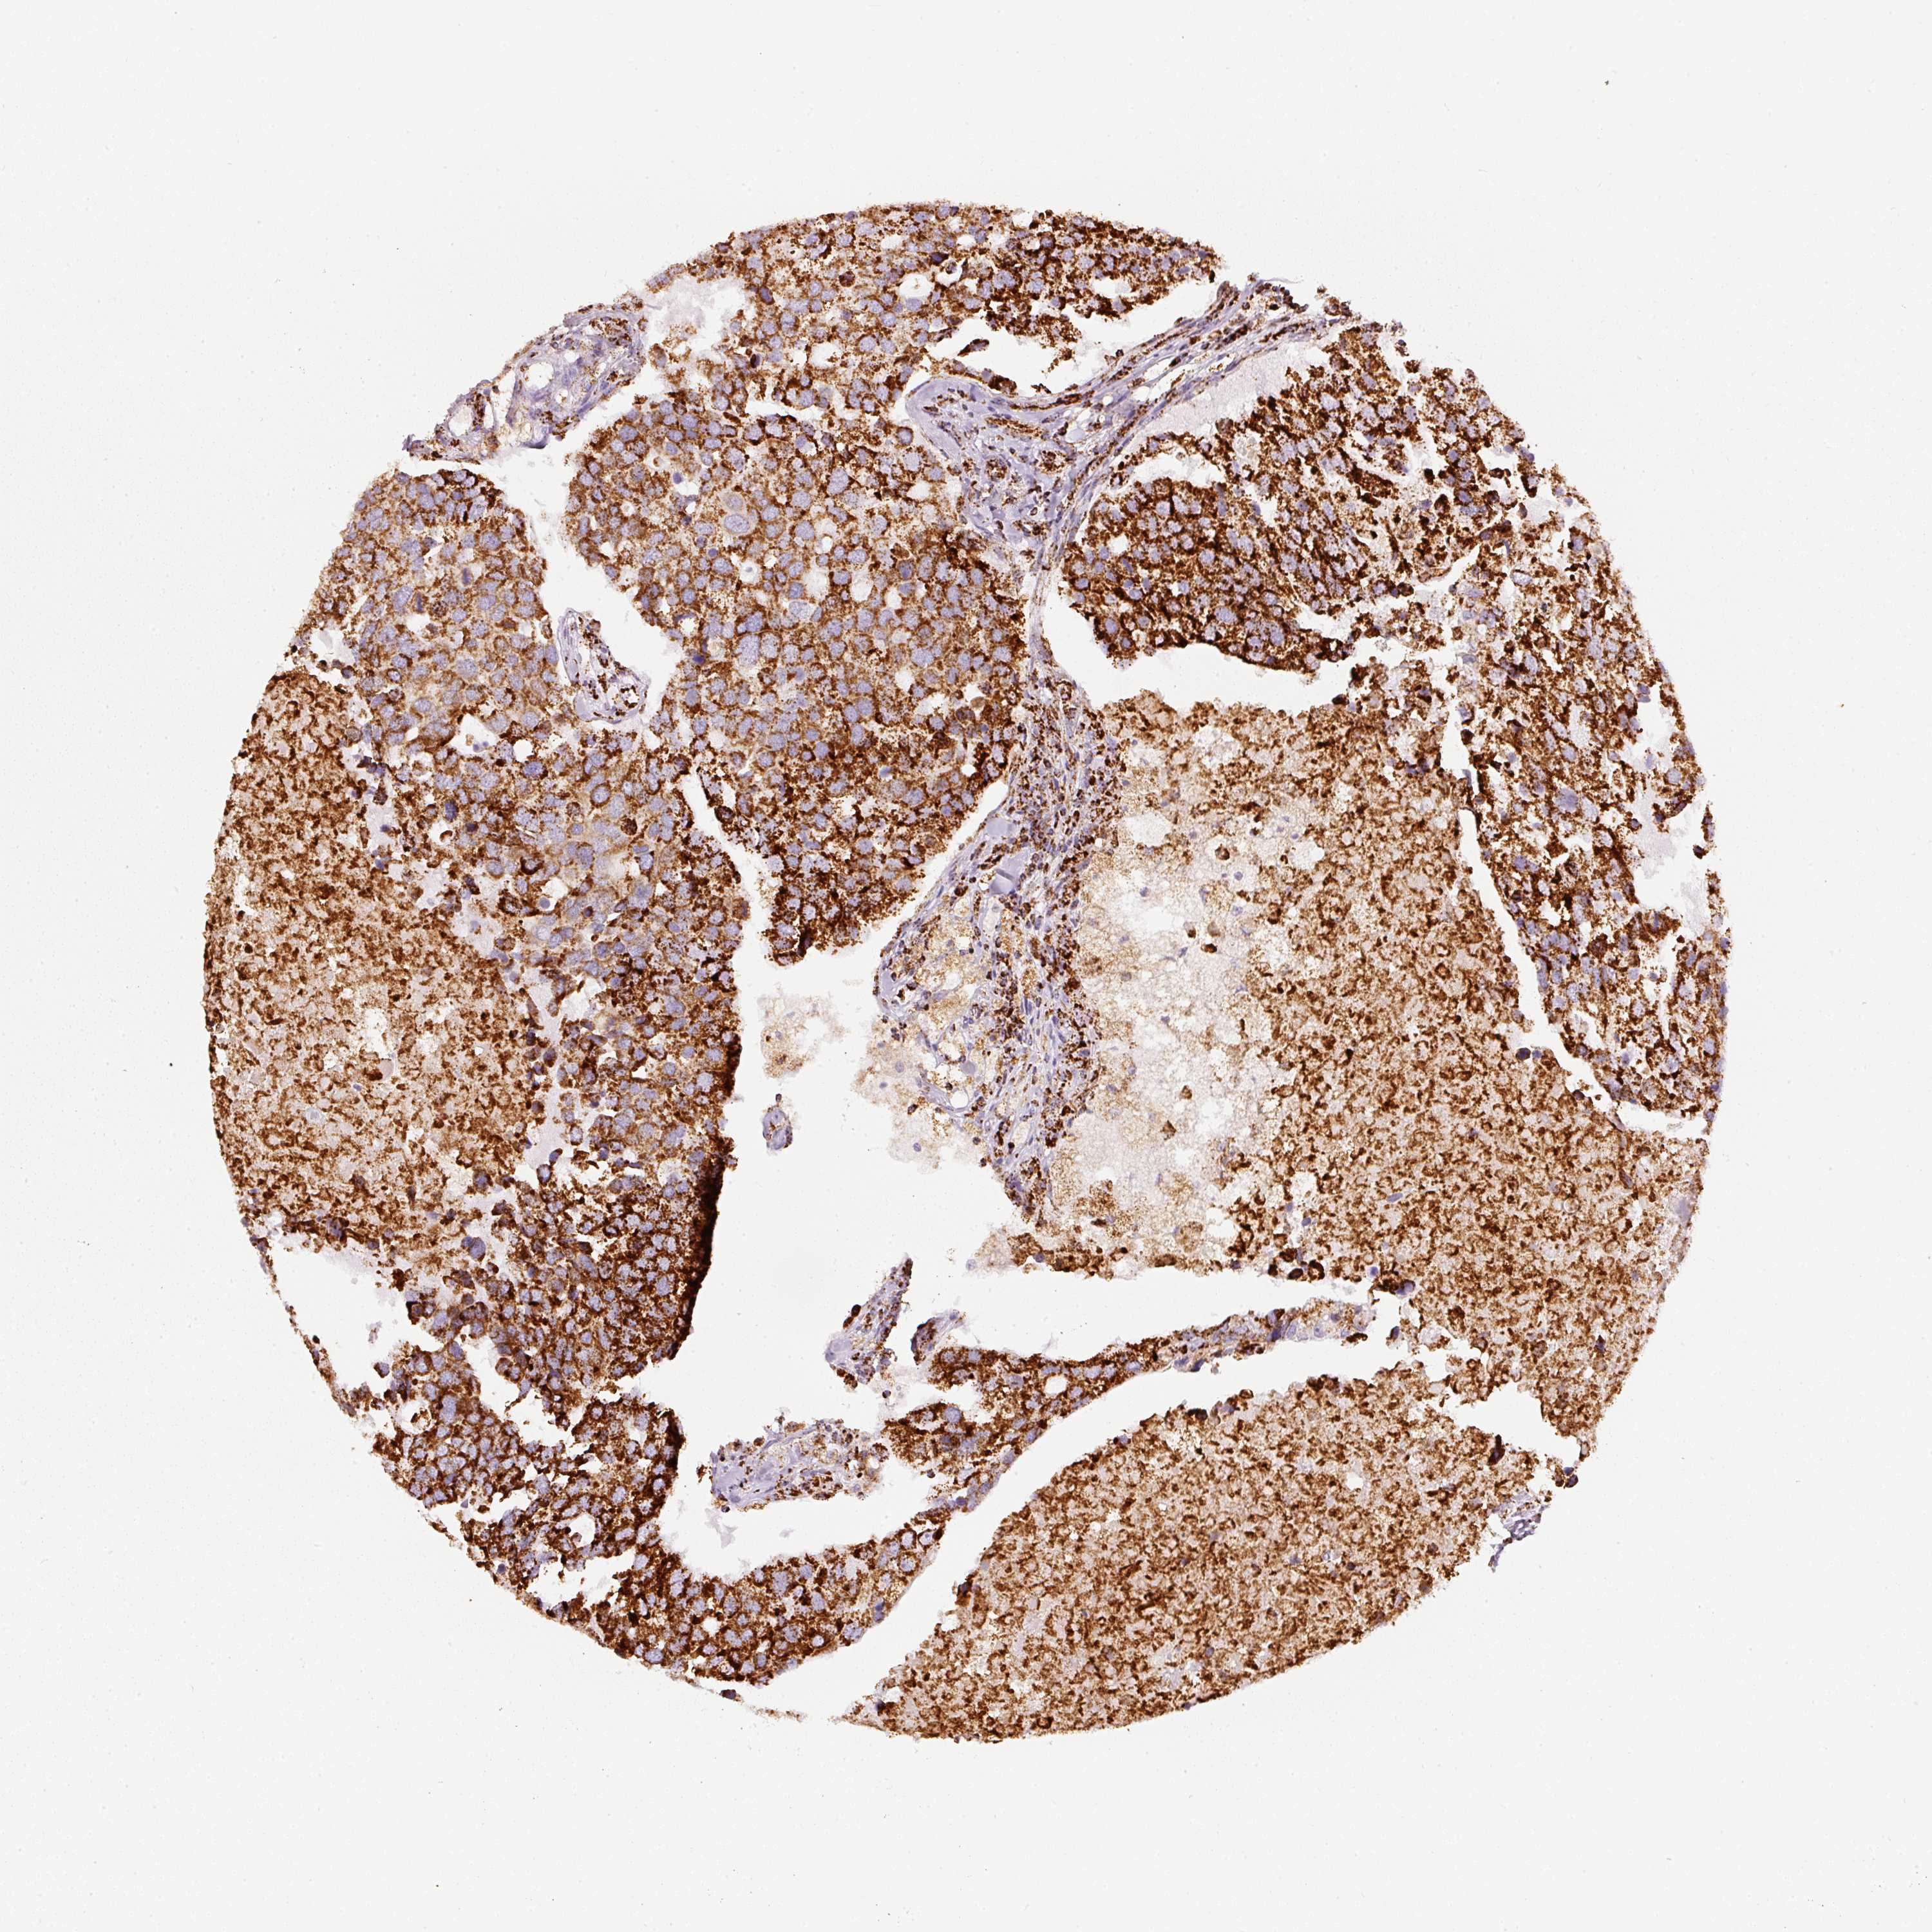

CANCER BREAST CANCER Show tissue menu

BRCA TCGA BRCA VALIDATION PROTEIN EXPRESSION